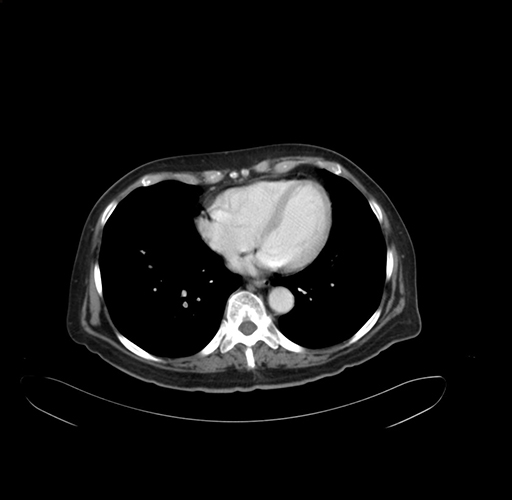

Pre-Chemo: Axial Venous

Axial Venous